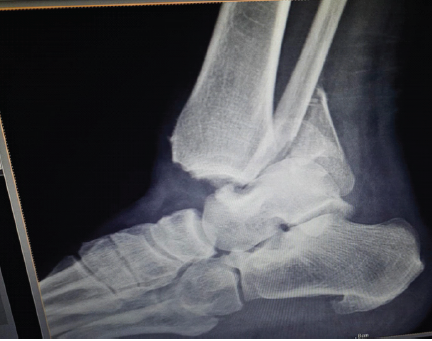

Single-Stage Hybrid Fixation of a Grade III Open, Unstable Trimalleolar Ankle Fracture with Syndesmotic Disruption and Posterior Talar Subluxation

Jeff Walter Rajadurai OR , C S Likhit , Shailesh Kumar , K Purushothaman , D Sudharsan , Naveen Kumar Duraisamy

………………………………p.101-105